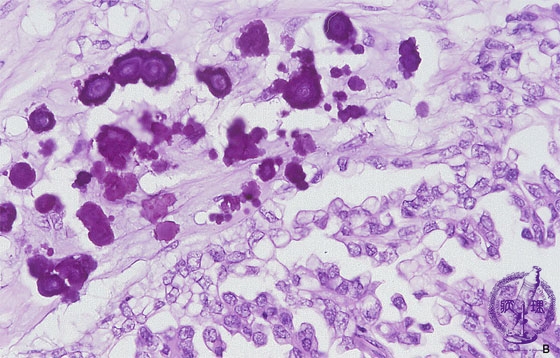

Histology (HE stain, high power): Serous cystadenocarcinoma of the ovary. Calcium deposition called psammoma body can sometimes be identified.

Click the image to see the enlarged image.